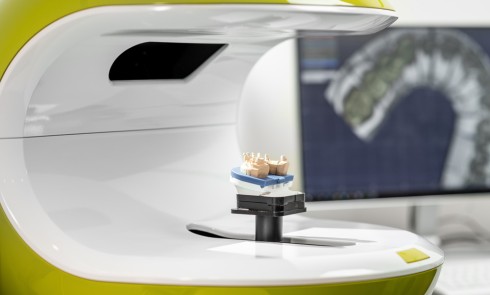

La prise en charge de ces édentements nécessite un examen complet du site implantaire et de l’environnement [16]. Les conséquences du non-remplacement rapide que nous venons d’énumérer sont à prendre en compte et à corriger pour une intégration optimale de la restauration prothétique implantaire. Ainsi, des corrections orthodontiques peuvent être nécessaires avant ou pendant la thérapeutique implantaire.

Le temps de l’ostéointégration, des versions ou migrations sont aussi possibles et le recours à des dispositifs de maintien de l’espace peut se révéler indispensable (fig. 22 et 23).